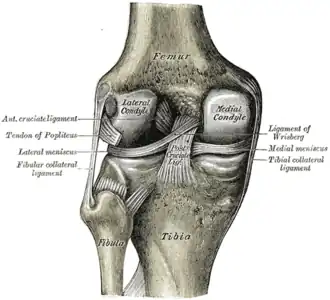

O joelho é uma articulação do corpo humano e de outros mamíferos. Formada pela extremidade distal do fêmur, pela extremidade proximal da tíbia (e pela patela (rótula).

O joelho ainda possui ligamentos que estabilizam a articulação, auxiliados pelos meniscos (interno ou medial e externo ou lateral), que estabilizam o joelho, e amortecem os impactos sobre as cartilagens.

Ligamentos

| Nome | Cápsula | Origem | Inserção | Descrição |

| ligamento cruzado anterior (LCA) | dentro | côndilo lateral do fêmur | área intercondilar anterior | O papel do LCA é prevenir o deslizamento anterior excessivo da tíbia em relação ao fêmur |

| ligamento cruzado posterior (LCP) | dentro | côndilo medial do fêmur | área intercondilar posterior | A lesão deste ligamento é incomum, mas pode ocorrer resultando de uma força de tração traumática do ligamento. Este ligamento previne o deslizamento posterior excessivo da tíbia em relação ao fêmur. |

| ligamento capsular | - | - | - | - |

| ligamento patelar | fora | patela | tuberosidade da tíbia | - Também Chamado de Tendão Patelar pelo motivo de nao existir uma separação definida entre o tendao do quadriceps (o qual envolve a patela) e a area conectando a patela à tibia. Este forte ligamento ajuda no mecanismo de alavanca da patela e também funciona como tampão para os côndilos femorais. |

| ligamento colateral medial ou ligamento colateral tibial (LCM) | fora | epicôndilo medial do fêmur | condilo tibial medial | O Ligamento Colateral Medial protege a parte medial do joelho de ser aberto por uma força aplicada nas laterais do joelho (joelho valgo). |

| ligamento colateral lateral ou ligamento colateral fibular (LCL) | fora | epicôndilo lateral do fêmur | cabeça da fíbula | o Ligamento Colateral Lateral protege as laterais do joelho de uma força dobrante interior (joelho varo). |

| ligamento poplíteo oblíquo | fora | côndilo externo do fémur | continuidade do tendão do semimembranoso | Expansão Tendinosa dos musculo semimembranoso. Fortalece a parte de trás da capsula |

| ligamento poplíteo arqueado | fora | área intercondilar da tíbia côndilo lateral do fêmur a seguir da cabeça fibular | Conecta para a porção medial da cabeça fibular | Este ligamento fortalece o joelho posterolateralmente e quando lesionado está em combinação com uma lesão do tendão PCL e poplítea. |

Menisco

Os meniscos são elementos cartilaginosos presentes na articulação do joelho que servem para proteger as extremidades dos ossos que se esfregam entre si e para efetivamente aprofundar os soquetes tibiais dentro dos quais o fêmur se prende. Eles também possuem papel na absorção de choque mecânico. Existem dois meniscos em cada joelho, o menisco medial e o menisco lateral. Um deles ou ambos podem ser lesionados, quando o joelho é rodado ou dobrado com força acima do normal, e ou sofre grande impacto.